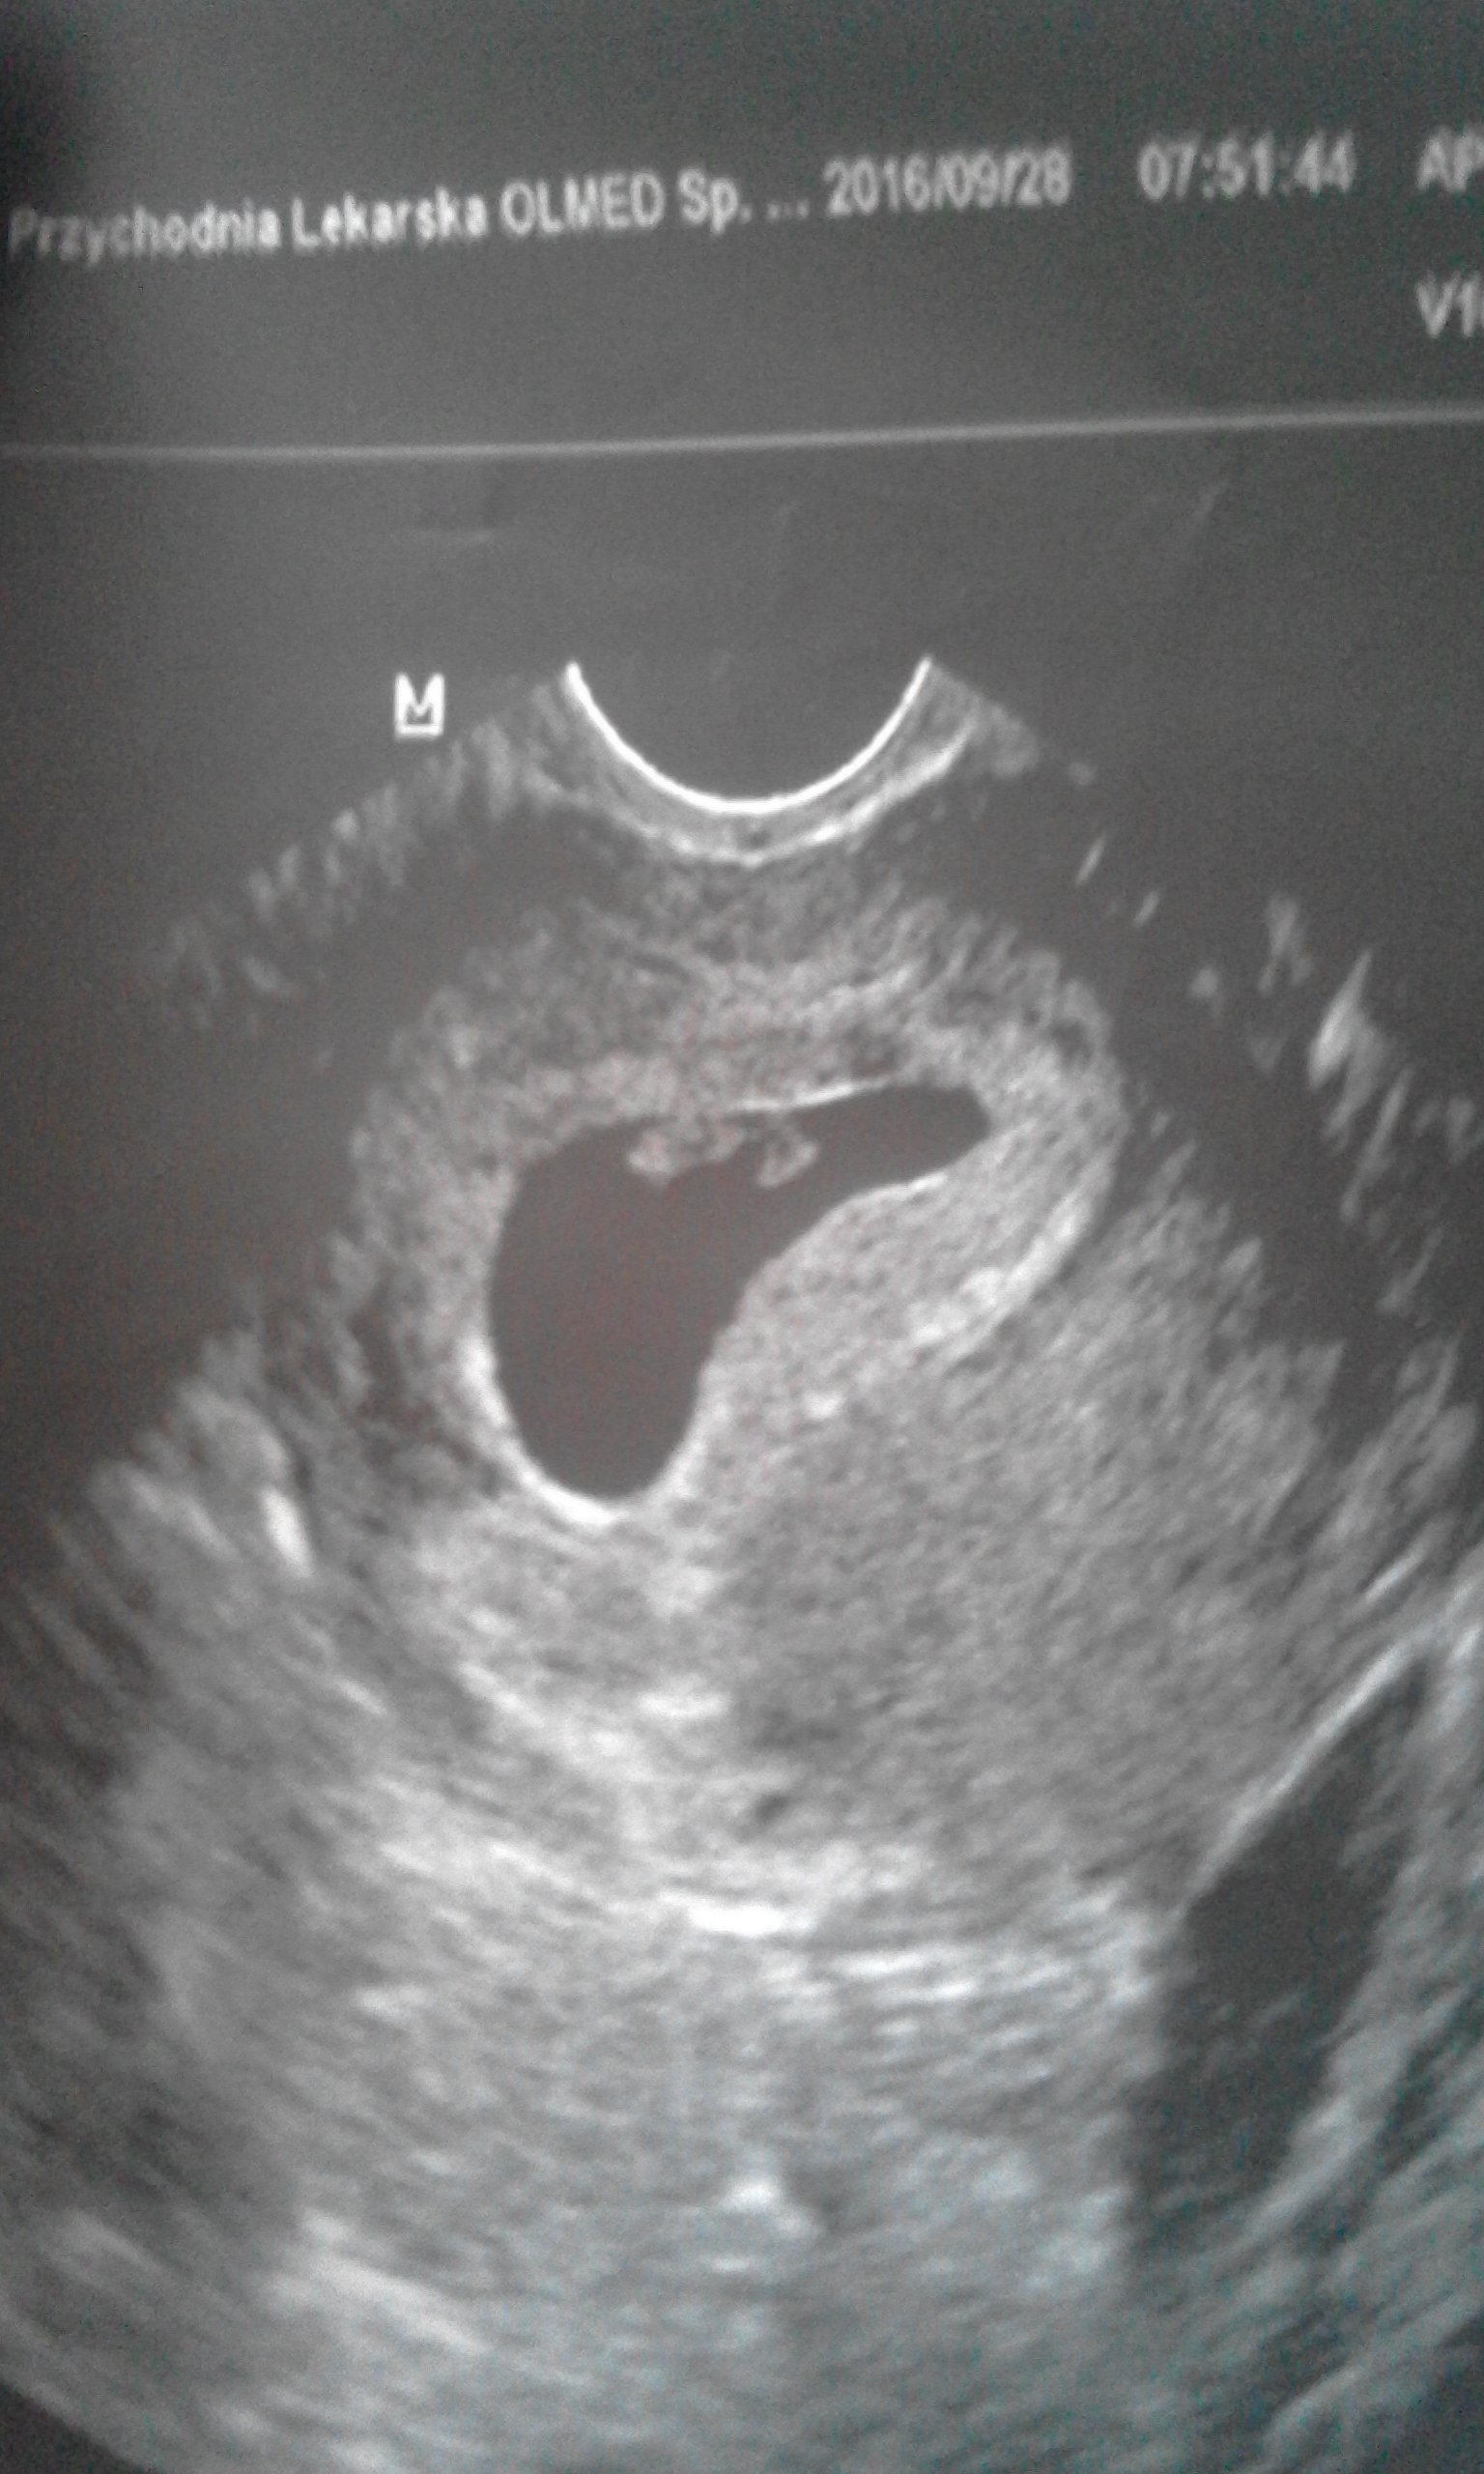

U mnie też to była wczesna ciąża 5/6 tc, co innego chyba się czuje jak ciąża jest starsza - nawet taka jak teraz, ja mam wrażenie że tyle czasu już w niej jestem...W tedy nie widziałam serduszka, teraz już tak więc mogło by być trudniej po stracie. No ale zawsze można to sobie wytłumaczyć, że tak musiało być, że dziecko źle się rozwijało, że natura wie co robi....więc ja staram się jakoś bardzo nie nakręcać tą ciąża i to 12 tyg mieć do tego trochę dystansu, że wszystko może się zdarzyć...